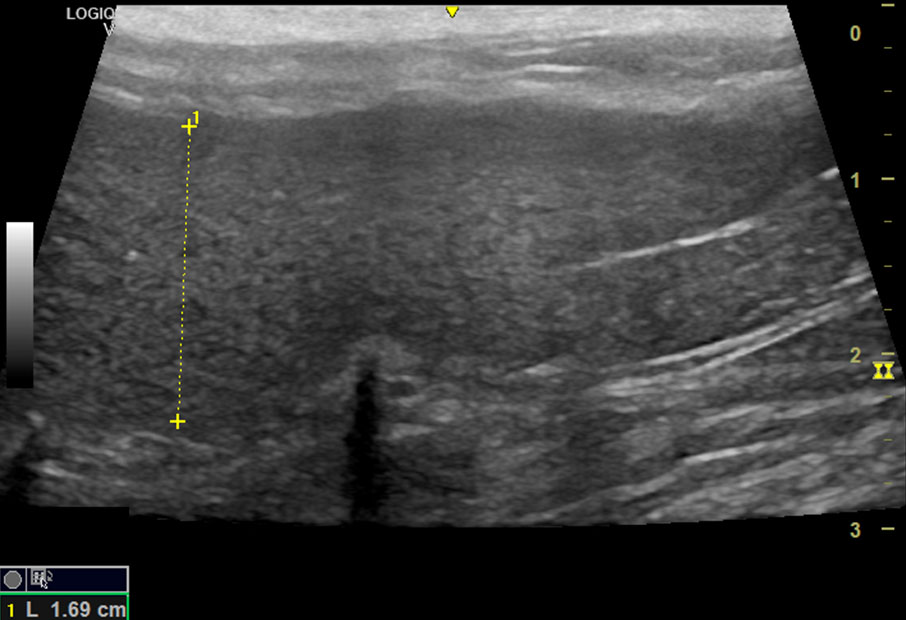

En la ecografía abdominal se detectaron diferentes alteraciones compatibles con PIF como sería: aumento de ecogenicidad del peritoneo, ganglios aumentados de tamaño e hipoecoicos, esplenomegalia y parénquima esplénico heterogéneo y alteraciones a nivel renal consistentes en irregularidad de la capsula, pérdida de diferenciación corticomedular y presencia de estructuras hiperecogénicas en la cortical compatibles con granulomas entre otros (ver video).